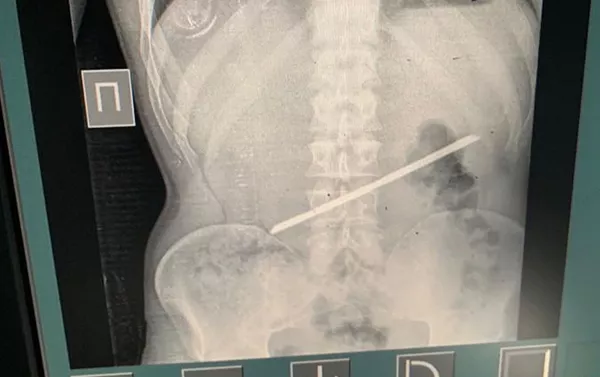

БИШКЕК, 29 сен — Sputnik. В Алматы врачи извлекли из желудка пациента 25-сантиметровый кусок арматуры, пишет Sputnik Казахстан.

В Алматы врачи извлекли из желудка пациента 25-сантиметровую арматуру

С арматурой в желудке мужчина прожил 2,5 года, и только сейчас обратился с проблемой к врачам. Со слов пациента, более двух лет назад он находился в следственном изоляторе, где и проглотил арматуру.

Как сообщили в Управлении здравоохранения Алматы, мужчина прожил с инородным телом в желудке 2,5 года и только сейчас обратился к врачам. По словам казахстанца, более двух лет назад он находился в следственном изоляторе, где и проглотил арматуру.

"28 сентября он сам пришел в больницу с жалобами на острые боли в эпигастральной области. Слова пациента подтвердились в результате рентген-диагностики, мужчину сразу взяли на операцию. Проведены лапаротомия и гастротомия, инородное тело удалено. Операция прошла успешно, пациент переведен в палату пробуждения", — рассказал хирург Темирхан Кожахметов.

Отмечается, что удаление инородного тела из организма — операция несложная. Медицинская бригада из шести человек провела ее за 54 минуты. Уникальность случая в том, что более двух лет металлический предмет в желудке не доставлял проблем, не мигрировал и не повредил стенки органа.